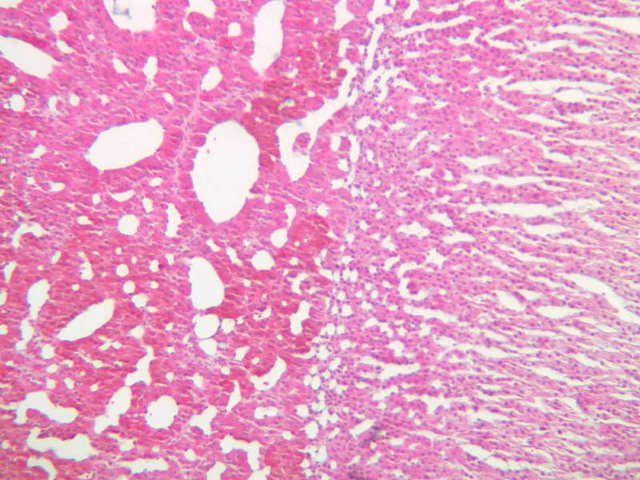

The adrenal gland (slide B-59, H&E [2.5x-labeled, 10x-labeled, 20x, 40x-labeled] [2.5x, 10x-labeled, 20x, 40x]; B-60, H&E [2.5x-labeled, 10x, 20x, 40x]; B-62, H&E [10x, 20x, 40x] [2.5x, 10x]) is a composite organ consisting of two functionally, structurally and embryologically different parts—an outer cortex and an inner medulla. Observe the gland at low power. Find the loosely organized tissue that comprises the medulla and the partially-separated columns of cells that make up the cortex. Scan the capsule and the tissue around it, looking for nerves and blood vessels. Study the pattern of cortical vasculature. In a pattern similar to that seen in the pars distalis of the pituitary, sinusoids run along the edges of columns or cords of cells. Owing to different arrangements of its constituent cells, the adrenal cortex has a layered appearance. From the capsule inward, these cortical layers are known as the zona glomerulosa, the zona fasciculata, and the zona reticularis.

The zona glomerulosa is located immediately beneath the capsule (B-60 adrenal gland, dog [10x, 20x] [20x, 40x]; B-59 [2.5x, 10x, 20x] [2.5x, 10x, 20x]). Its constituent cells are arranged in arcs or spheres, and, owing to their relatively small size, their nuclei appear to be close together. Cells of the zona glomerulosa secrete mineralocorticoids (e.g., aldosterone). The zona fasciculata consists of parallel columns or cords of cells that radiate toward the medulla and are separated by blood sinusoids (B-60 [2.5x, 10x, 20x, 40x]; B-62 [20x, 40x]). Owing to the extraction of lipids during histological processing, the cytoplasm of cells in the zona fasciculata appears highly vacuolated or "foamy". Cells of the zona fasciculata secrete glucocorticoids (e.g., hydrocortisone & cortisone) and some gonadocorticoids (weak androgens). The zona reticularis is the deepest cortical layer and lies adjacent to the medulla (B-60 [20x, 40x]; B-62 [20x, 40x]). It is characterized by irregular, interconnecting cords of cells which are separated by anastomosing capillary networks or sinusoids. Cells of the zona reticularis, which are smaller than those of zona fasciculata and do not contain as many lipid vacuoles, secrete gonadocorticoids and some glucocorticoids.